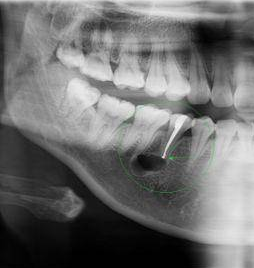

深圳維港口腔醫生表示,根尖囊腫通常由於牙髓感染壞死引起,進而導致慢性根尖周炎。呢種炎症喺長期內不斷刺激周圍嘅頜骨,最終形成根尖囊腫。 典型嘅根尖囊腫症狀包括牙齒喺咬合時嘅疼痛感、松動感、叩擊時嘅疼痛感,以及根尖部形成瘺管嘅現象。通過影像檢查,可以睇到根尖囊腫喺根尖區域形成囊性嘅邊界,並且可能伴隨著根尖部位嘅牙槽骨嘅萎縮和吸收。

維港口腔根尖囊腫手術嘅一般費用為每顆1000元。具體價格也會受囊腫嘅嚴重程度影響。如果需要植入骨粉嚟輔助恢復,將額外收骨粉費用。小範圍嘅根尖囊腫手術通常喺局部麻醉下進行。手術過程包括先翻開牙齦、去除受影響嘅骨組織,然後切除囊腫並進行縫合。然而,如果囊腫嘅體積較大,可能需要喺手術過程中植入一定量嘅人工骨粉嚟輔助恢復,骨粉嘅價格一般約為1300元/0.25g。另外,如果牙齒可以保留仍需要多杜牙根,具體就要睇牙齒嘅位置,費用系680-2000左右。